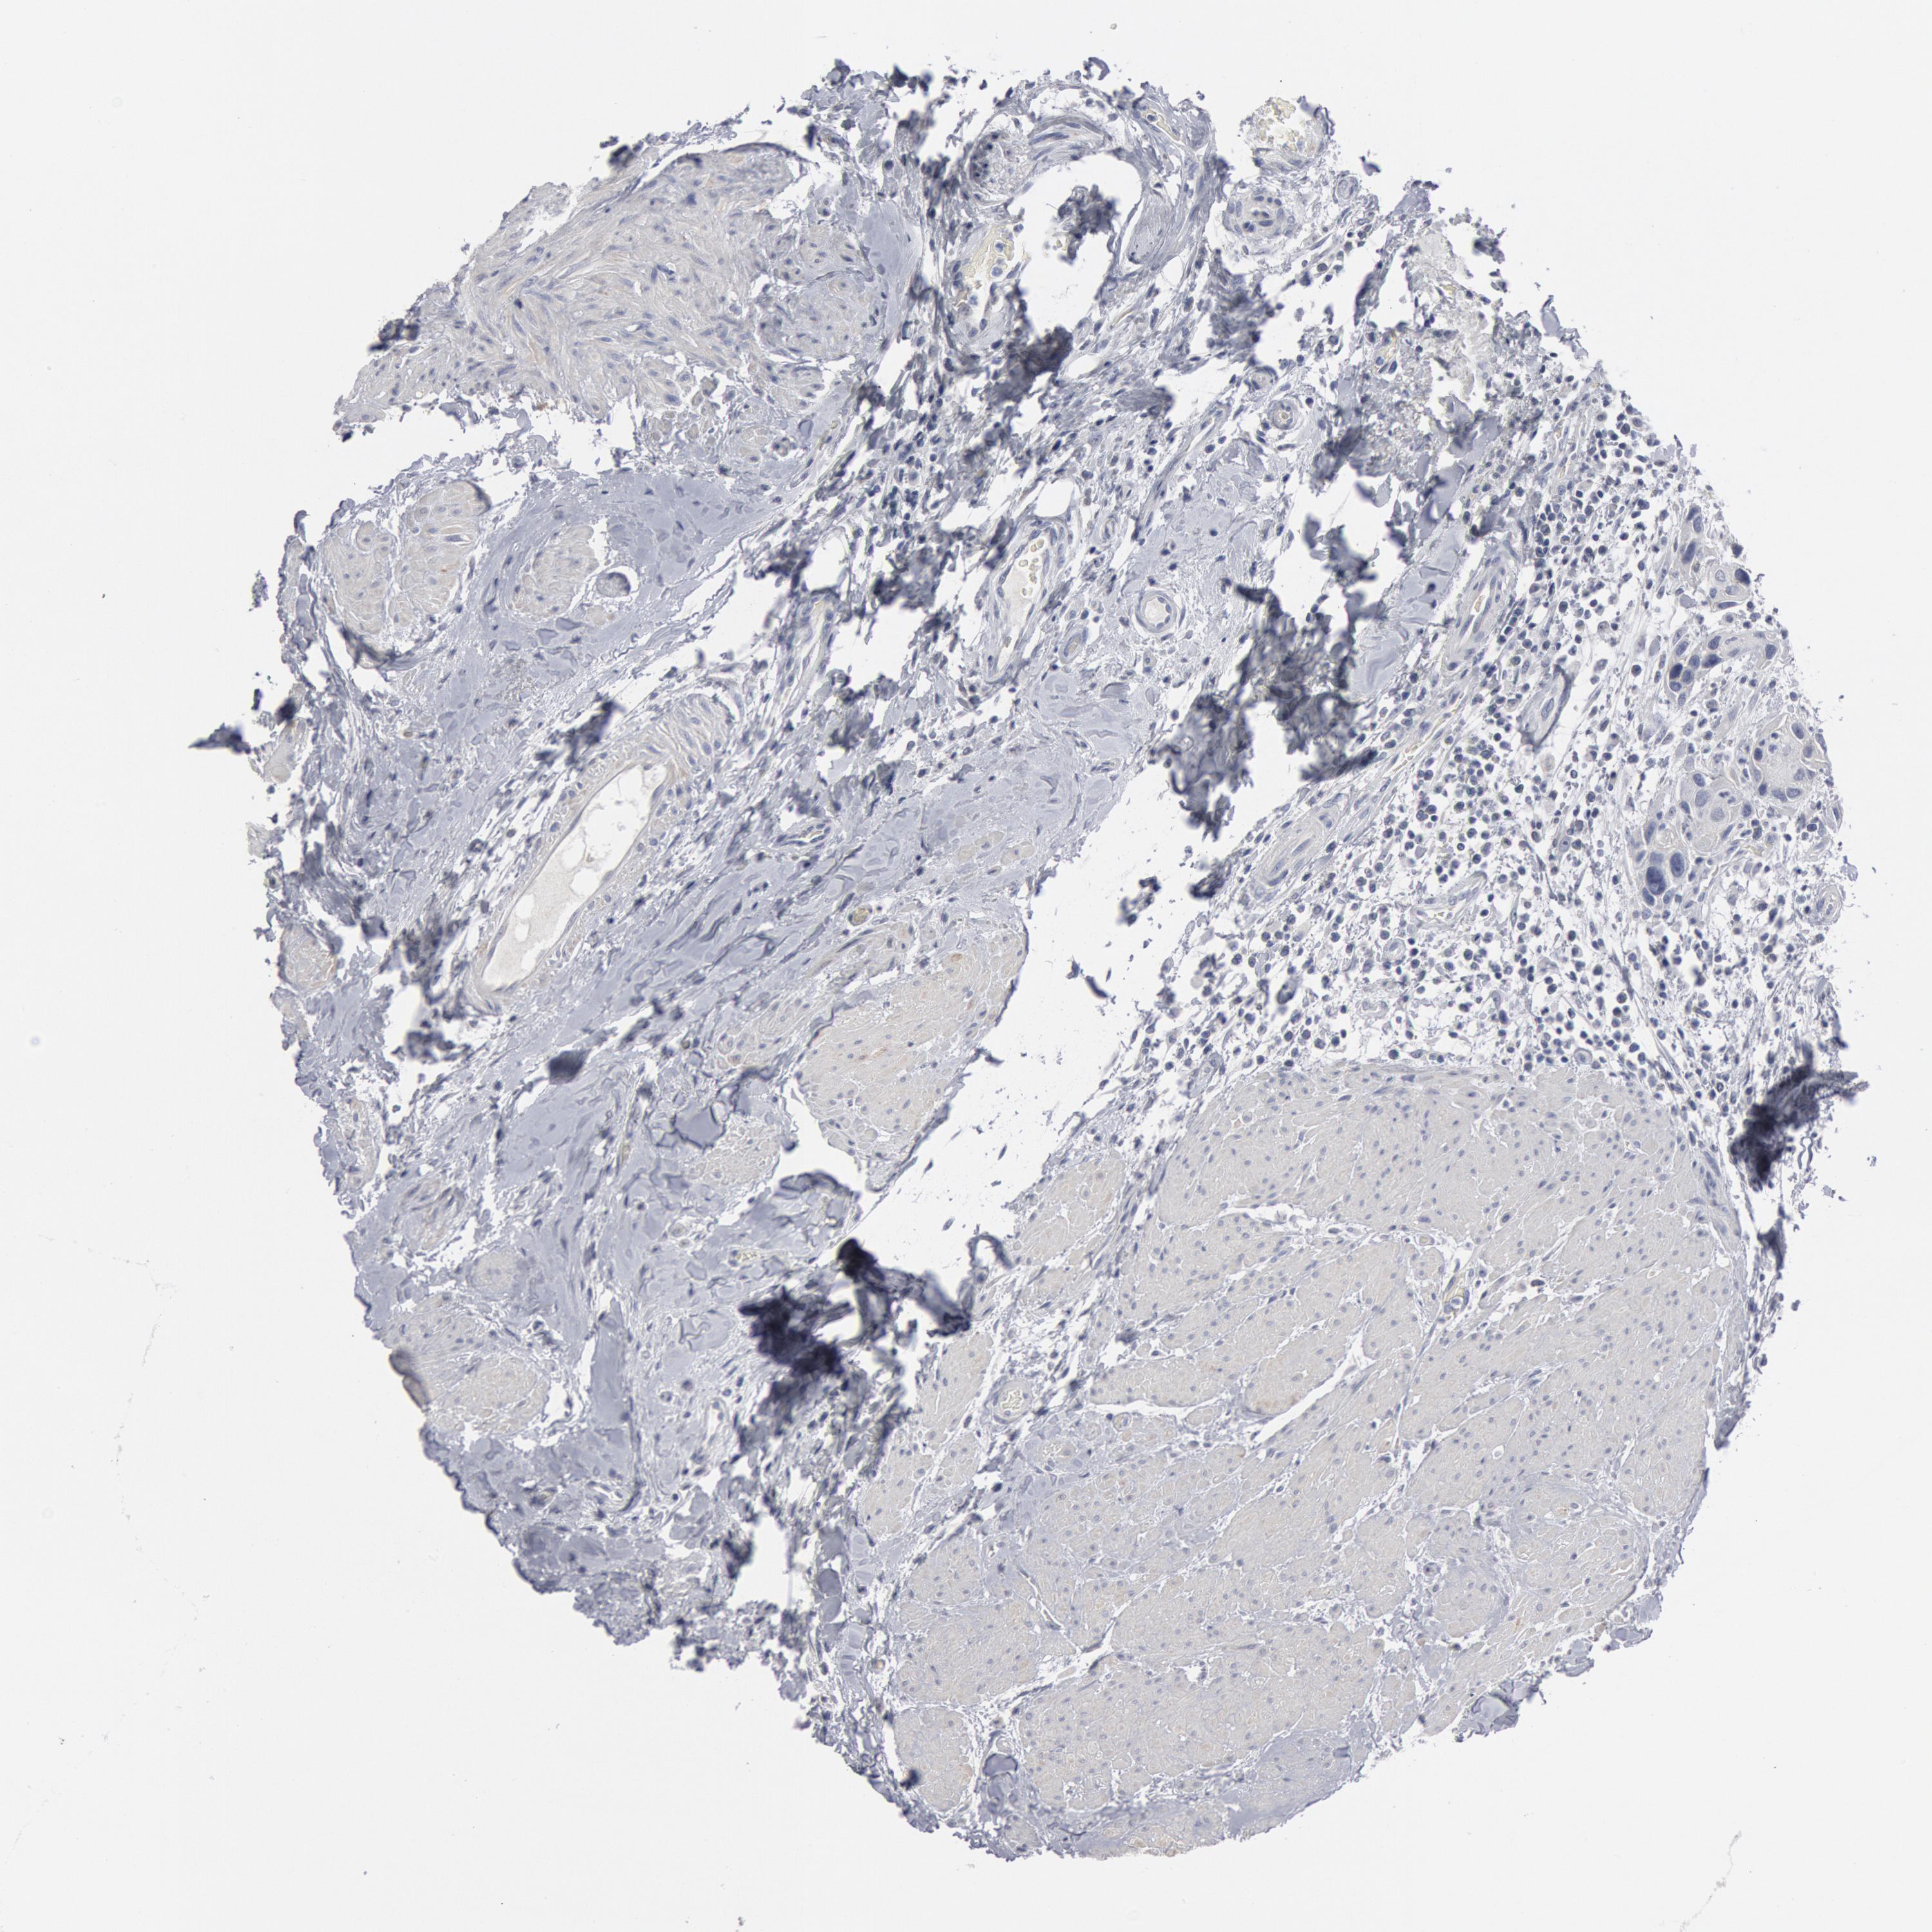

UROTHELIAL CANCER - Protein expressioni

A mouse-over function shows sample information and annotation data. Click on an image to view it in a full screen mode. Samples can be filtered based on level of antibody staining by selecting one or several of the following categories: high, medium, low and not detected. The assay and annotation is described here.

Note that samples used for immunohistochemistry by the Human Protein Atlas do not correspond to samples in the TCGA dataset.

Antibody stainingi

Antibody staining in the annotated cell types in the current human tissue is reported as not detected, low, medium, or high, based on conventional immunohistochemistry profiling in selected tissues. This score is based on the combination of the staining intensity and fraction of stained cells.

Each image is clickable and will lead to virtual microscopy that enables deeper exploration of all samples and also displays staining intensity scores, fraction scores and subcellular localization as well as patient and tissue information for each sample.

Antibody HPA001232

Antibody CAB015397

Urothelial carcinoma, High grade

Urothelial carcinoma, Low grade

Adenocarcinoma, NOS